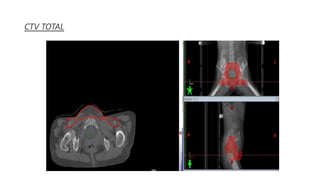

CTV TOTAL

PTV

Organs at risk

• #84 PTV EXPANSION INTO THE CUSTOM BOLUS FOR IMRT OPTIMIZATION